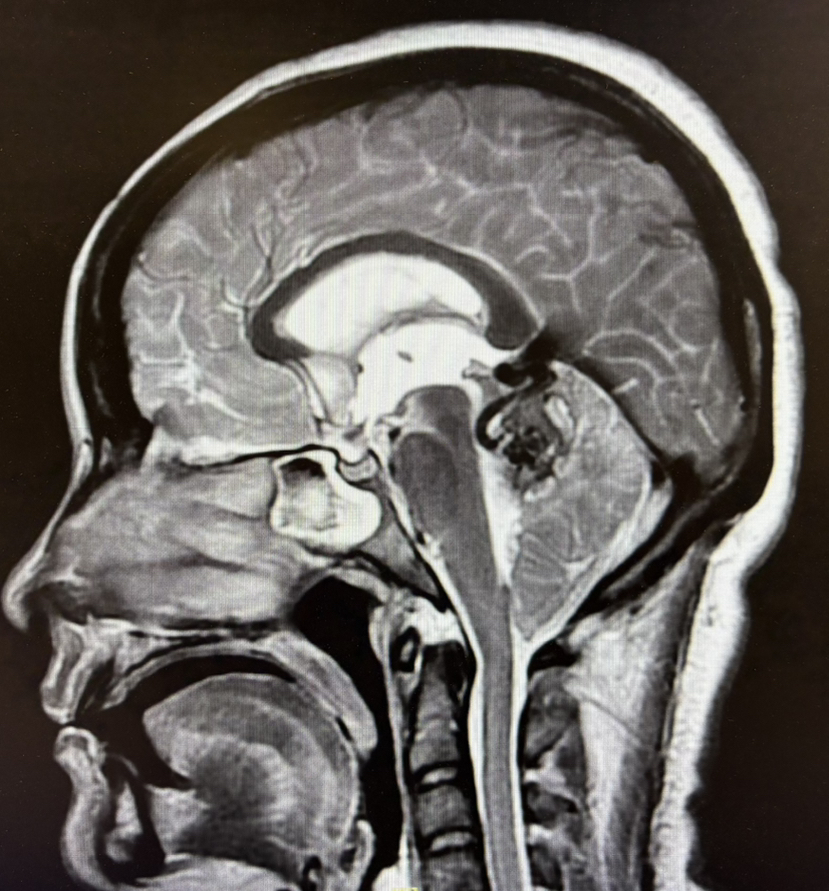

2期术前MRI